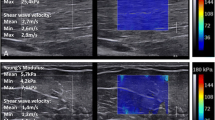

Shear wave elastography in an adult patient affected by cerebral palsy. In B mode the medial and lateral gastrocnemius muscles appear equally hyperechogenic, as seen on the background of the elastograms. The medial gastrocnemius (a) showed a shear modulus between 142 and 197 kPa, whereas the lateral gastrocnemius (b) showed a shear modulus between 24 and 36 kPa. This reflects an asymmetric involvement of these muscles, probably with a larger amount of fibrosis in the medial gastrocnemius. Note that in healthy individuals, the stiffness is greater in the lateral gastrocnemius